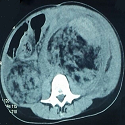

Néphrectomie bilatérale de sauvetage compliquant une sclérose tubéreuse de Bourneville

Mohamed El Amrani, Mounia Azizi

PAMJ. 2014; 19: 205. Published 24 October 2014